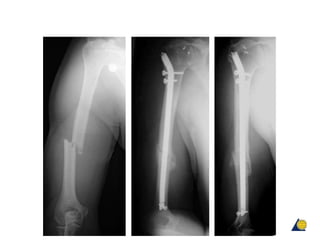

Humeral shaft fractures—antegrade

locked IM nails

• Pathological and

osteopenic fractures

• Good rotational/length

control

• Good healing rates

• Often allows weight

bearing